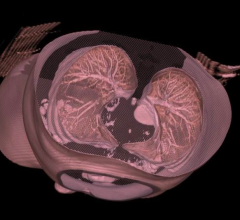

Contributing Editor Greg Freiherr offers an overview of computed tomography (CT) advances at the Radiological Society of North America (RSNA) 2015. The video includes Freiherr during his booth tours with some of the key vendors who were featuring new technology.

Computed Tomography (CT)